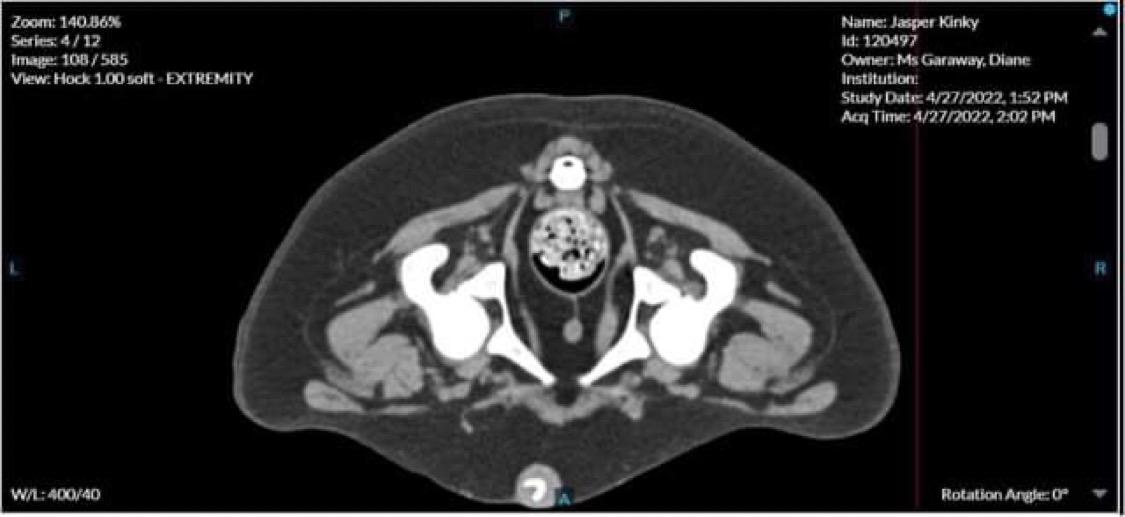

• Jasper’s CT scan results - update from Diane

Main image

Jasper’s CT scans came back, the tiny bone structures in his nose are destroyed, probably due to inflammation, they need to do more biopsies to rule out anything else.

His hips have quite bad dysplasia and will require surgery, possibly hip replacement.

He will need to stay on the Apoquel for life for his nose.

Hopefully the summary will be emailed at some stage, it was a bit overwhelming receiving the phone call from the specialist last night.

• Jasper update

Little Jasper had his CT scan today! Which cost Diane $4500, thank you everyone for your generous donations to help cover this.